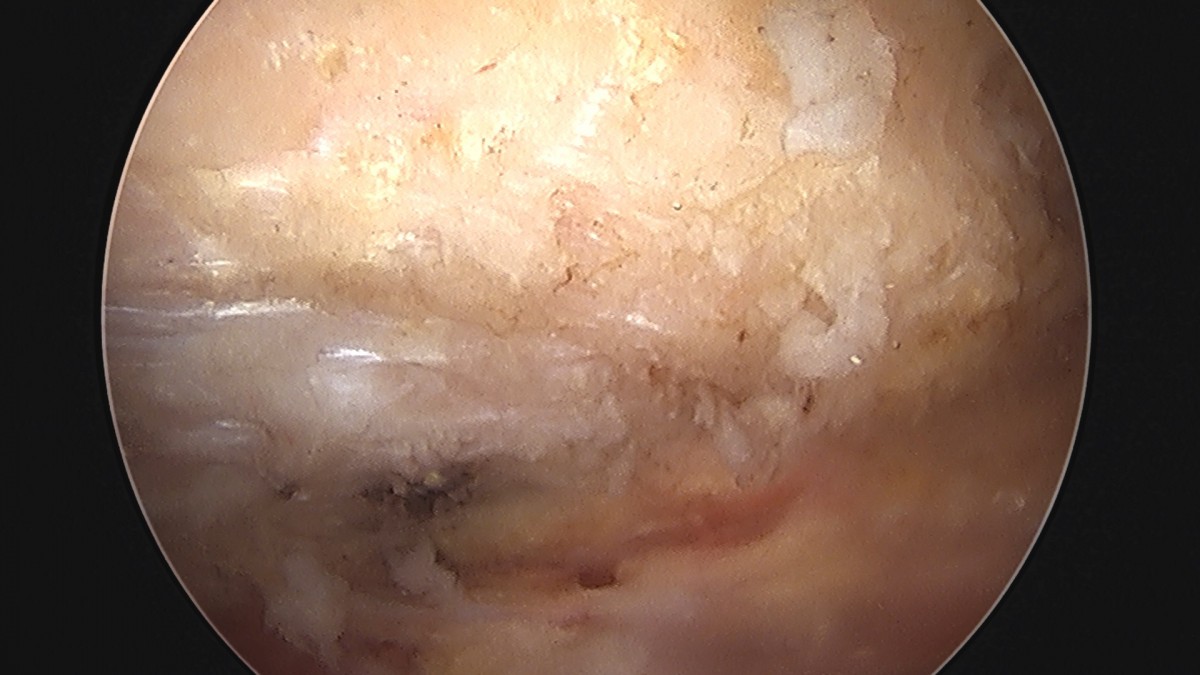

이재상원장님 어깨 회전근개 봉합술 및 견봉하 감압술, 관절낭 이완술 이희O 환자

dae765e4d9ac96aee867c9d6292d8784_1758004883_2867.jpg

dae765e4d9ac96aee867c9d6292d8784_1758004883_8742.jpg

dae765e4d9ac96aee867c9d6292d8784_1758004884_4543.jpg

dae765e4d9ac96aee867c9d6292d8784_1758004885_0448.jpg

dae765e4d9ac96aee867c9d6292d8784_1758004885_6392.jpg

dae765e4d9ac96aee867c9d6292d8784_1758004886_2481.jpg

dae765e4d9ac96aee867c9d6292d8784_1758004886_8566.jpg

dae765e4d9ac96aee867c9d6292d8784_1758004887_4546.jpg

dae765e4d9ac96aee867c9d6292d8784_1758004888_0341.jpg

dae765e4d9ac96aee867c9d6292d8784_1758004888_6433.jpg